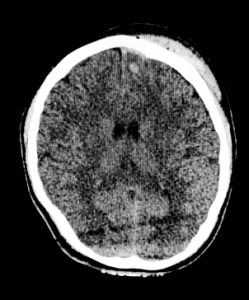

Shutterstock/AndaPhoto CT scan of subdural hematoma and intracranial hemorrhage.

CT scan of subdural hematoma and intracranial hemorrhage.